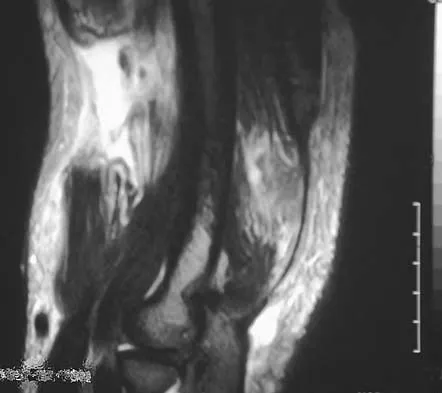

A 37-year-old man pulled his hamstring playing softball 3 weeks ago. The patient had not noted any mass prior to his injury. MRI scans of the posterior thigh are shown in Figures 4a and 4b. Figure 4c shows the biopsy specimen from a needle biopsy. What is the most likely diagnosis?

Malignant fibrous histiocytoma (MFH) is the most common soft-tissue sarcoma. MFH typically presents as a large mass, deep to the fascia with heterogeneous signal on MRI. The MRI scans show a heterogeneous lesion in the posterior thigh. There is significant high signal uptake on the T2-weighted image. The histology shows malignant histiocytic cells with marked atypia and pleomorphism. Histology of a hematoma would show only old hemorrhage and some granulation tissue. Lipoma and liposarcoma are both seen as a fat-containing lesion on histology. No significant fat tissue is seen in this histologic specimen. Histology of myositis ossificans would show bone formation. Simon SR (ed): Orthopaedic Basic Science. Rosemont, IL, American Academy of Orthopaedic Surgeons, 1994, pp 219-276.